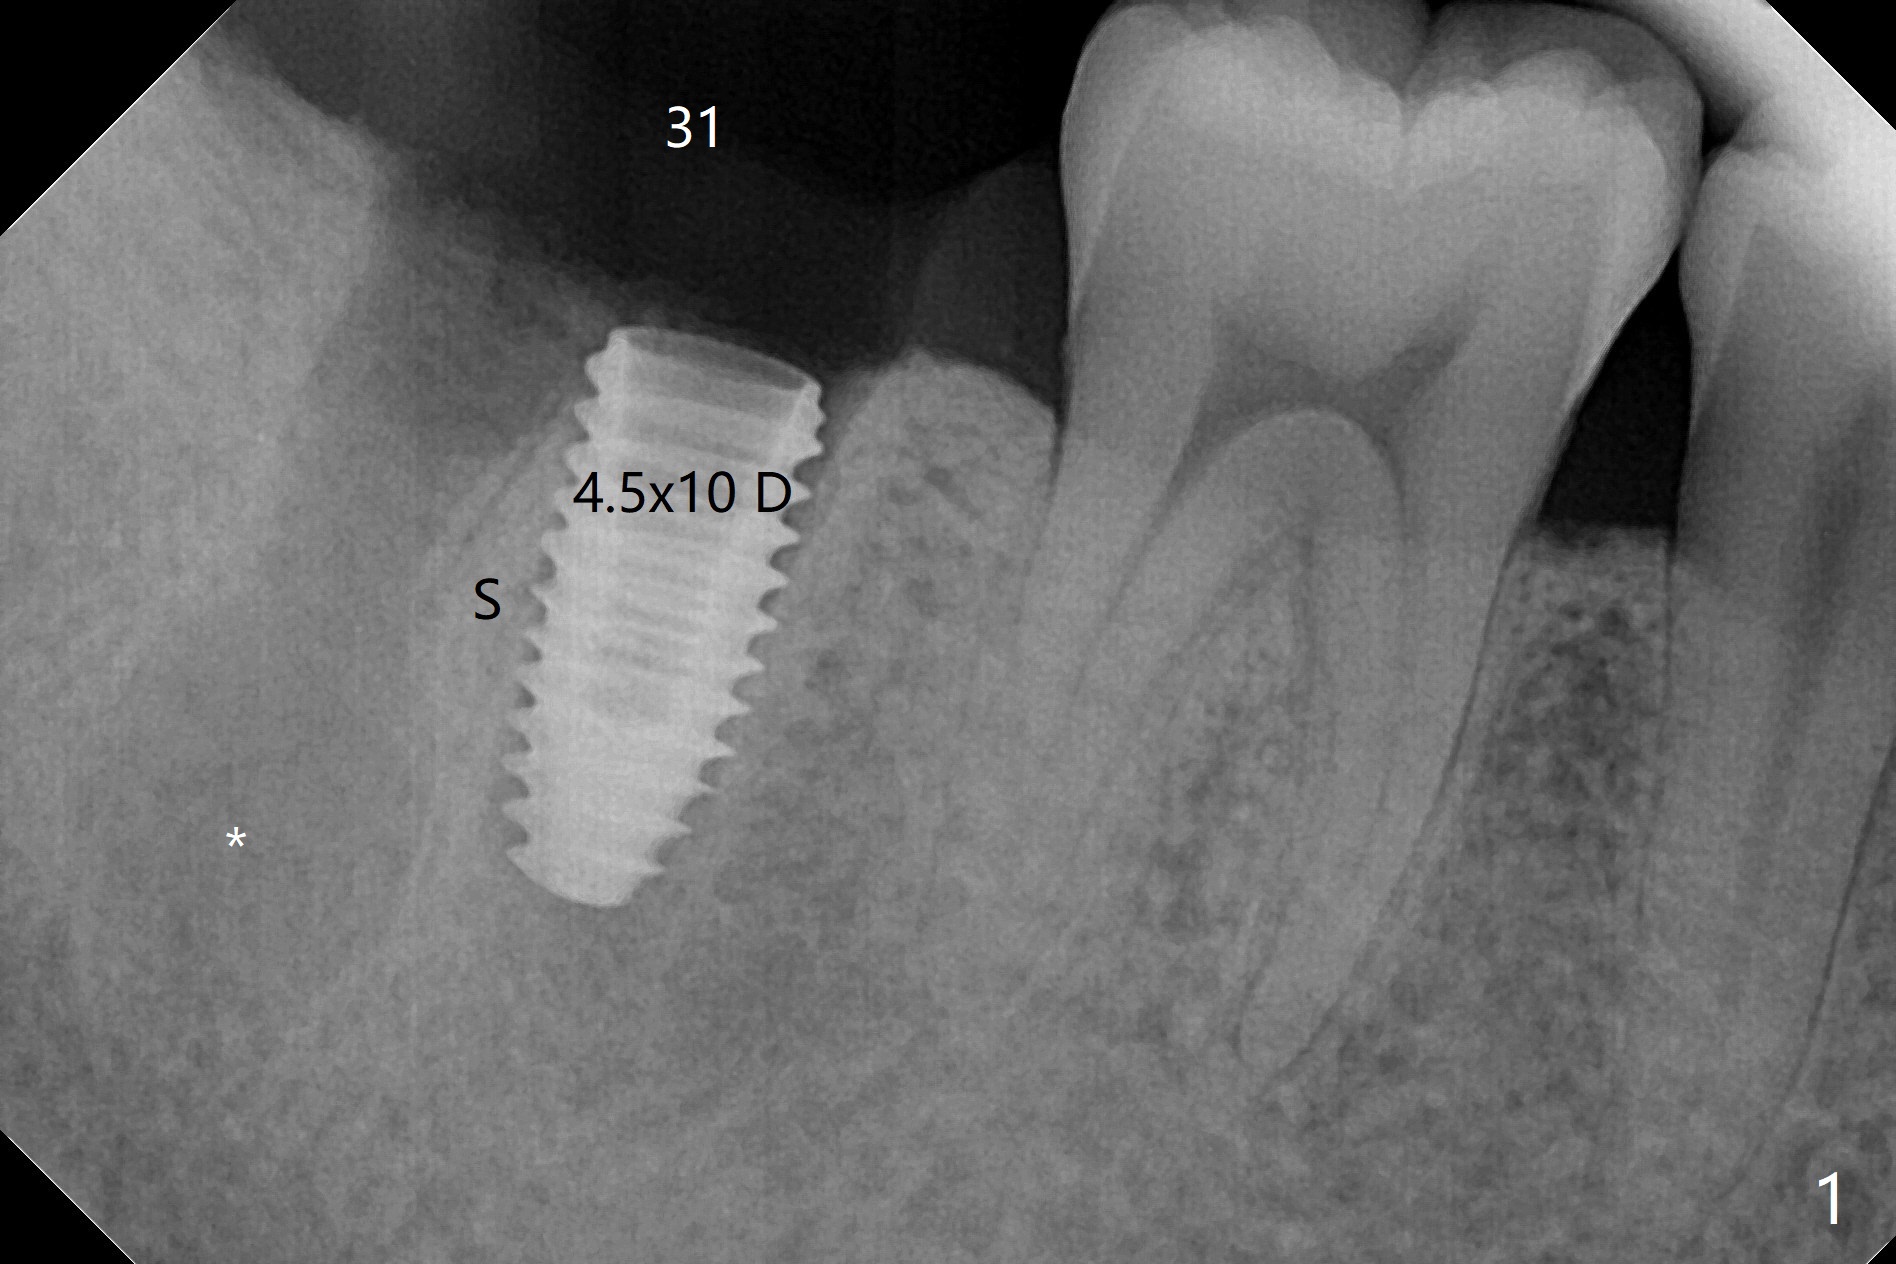

考虑到31号牙严重骨质吸收尤其是远中窝根尖(图一:*),实验室建议钻洞直径要比植体小三号(3.5毫米钻头;5.0毫米植体),其实行不通,使用4.0毫米钻头后,勉强植入4.5毫米报废植体(图一),阴差阳错:植体进入近中牙槽窝,植体四周都有骨壁包绕,包括远中:中隔(S)。最后为了使用5x11.5毫米植体,必须用4.5毫米钻头和5毫米皮质骨攻螺纹(到第三格,多3毫米,图二);放置基台好像没有就位。使用6毫米profile drill(好像去除舌侧中隔)后,手感基台就位,但是根尖片显示(图三)与图二没有区别(植体太粗,看不清楚植体与基台接触)。放置粘性骨粉后(图四),制作临时牙冠,放置PRF后,衬里多次增加固定和与牙龈密合度。术后医嘱包括手术区不使用水牙线。术后一周复诊询问骨粉游出问题。如果第二下磨牙种植能够进入近中窝,不必使用导板,4.5毫米足够,X光片观察基台就位也容易。术后三个月骨粉好像转变成正常骨质(图五,六, 30 Ncm)。